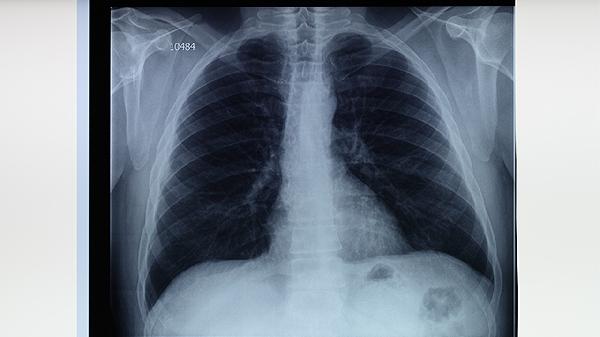

肺结核咳血护理方法有哪些

肺结核咳血可通过保持呼吸道通畅、调整体位、饮食调理、心理疏导、遵医嘱用药等方式护理。肺结核咳血通常由结核分枝杆菌感染引起,表现为咳嗽、咯血、低热等症状。